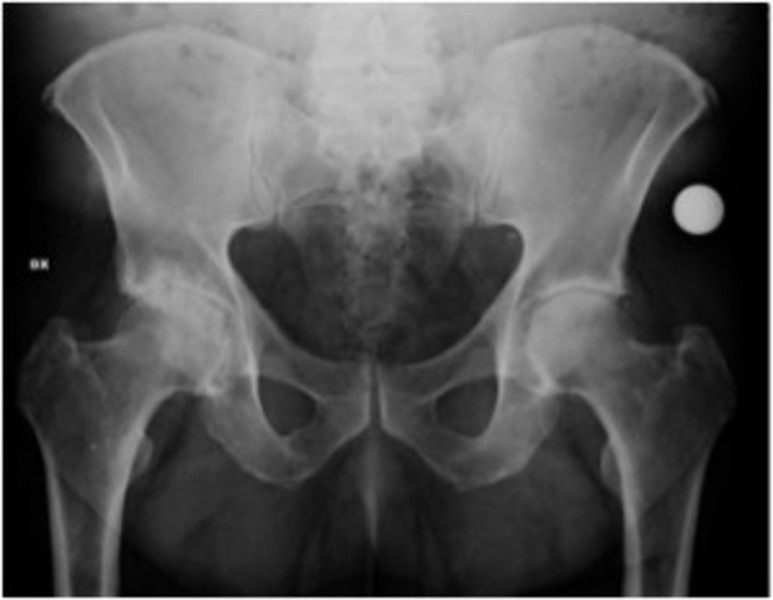

È una paziente oncologica, la sua patologia ne sta minando la stabilità delle gambe e, per questo motivo, il medico curante le ha prescritto una radiografia delle anche, con urgenza. Nonostante l'indicazione del cosiddetto «codice 48» che consente a chi soffre di questi problemi di accorciare i tempi di attesa per gli esami strumentali, l'appuntamento con la radiografia le è stato fissato al 30 giugno 2017.